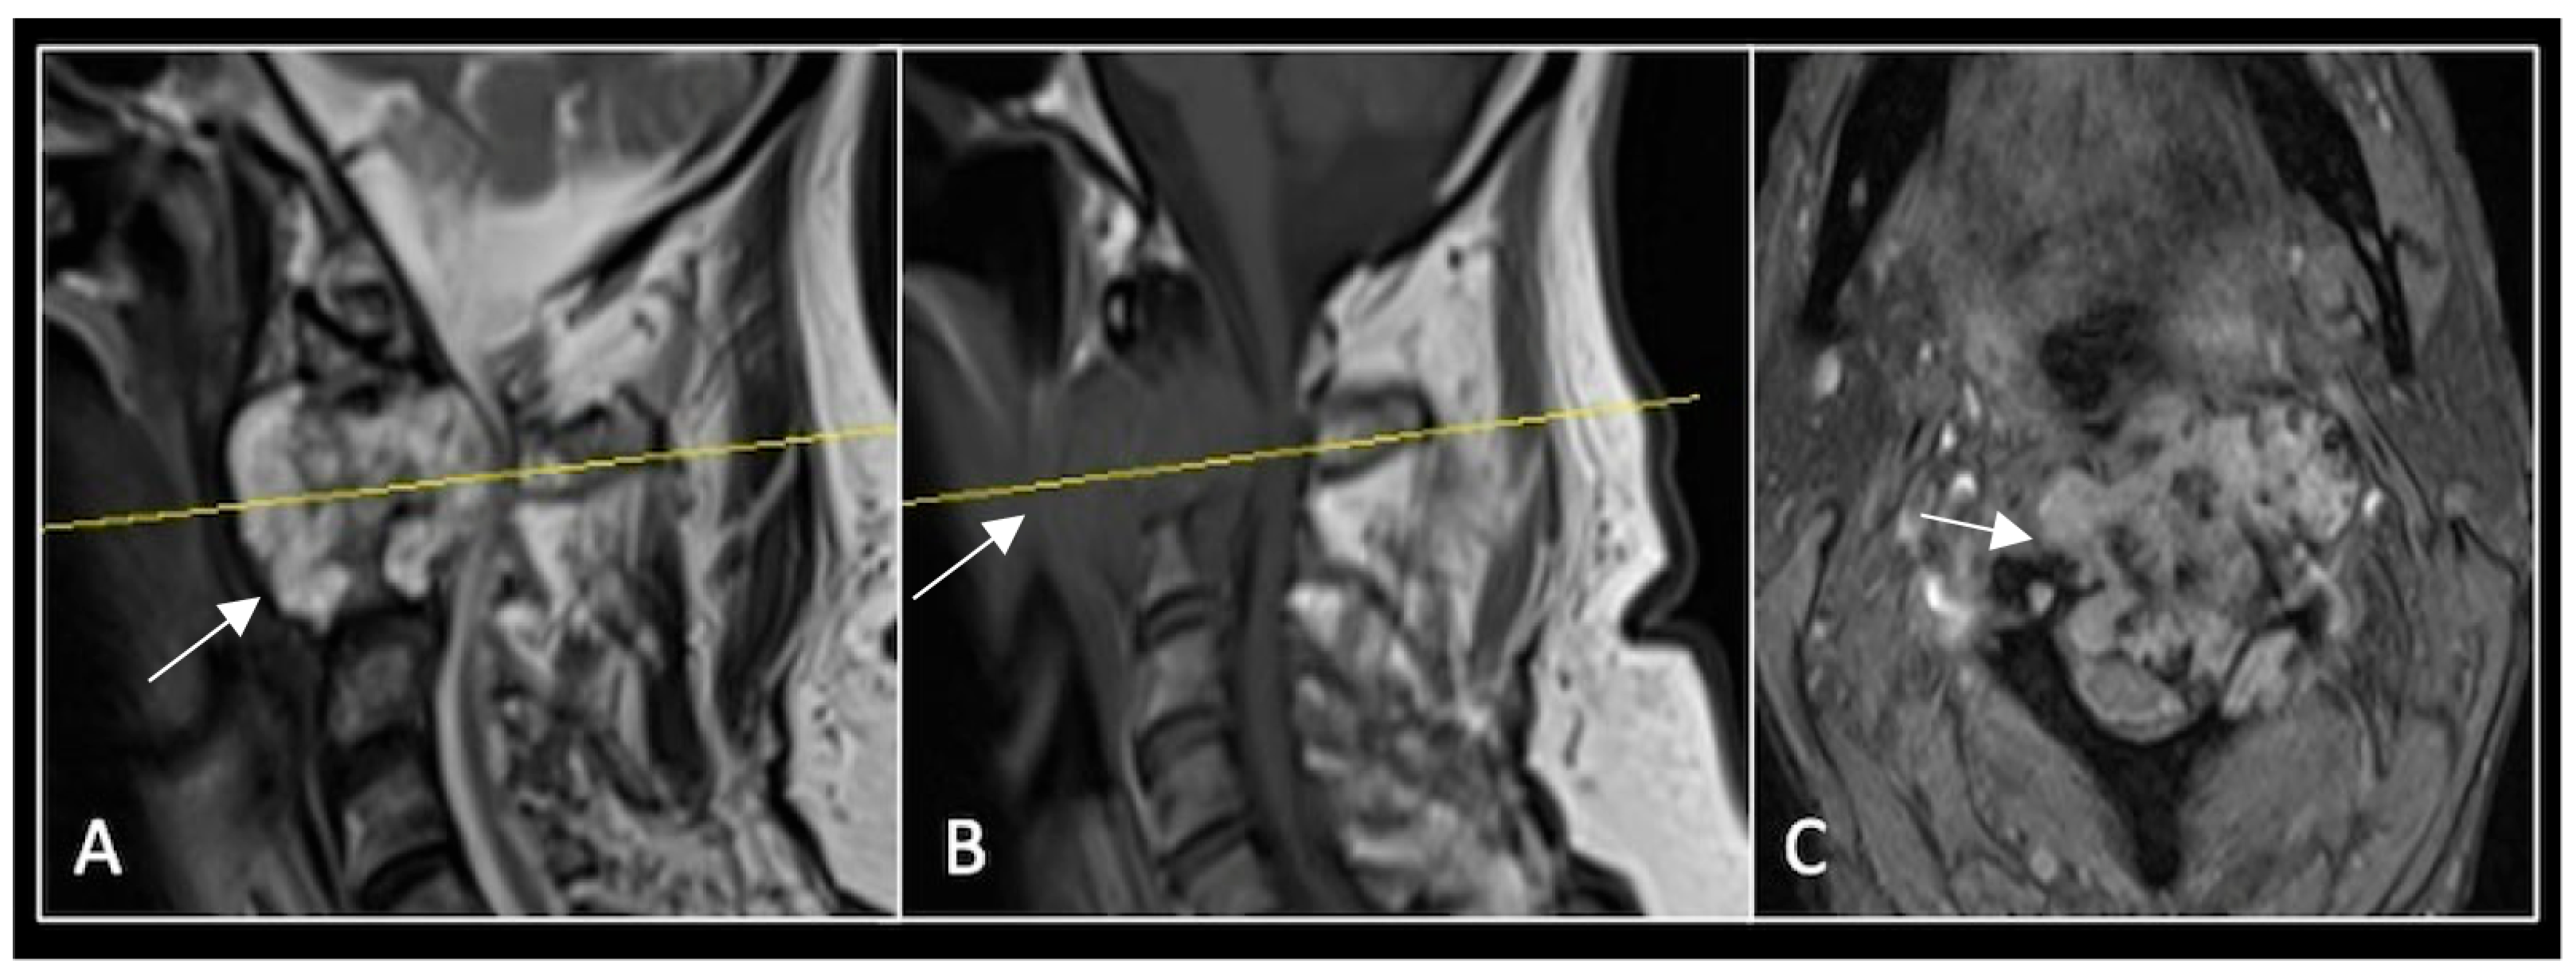

This 68-year-old male was referred to our institution with a 4 cm cervical mass localised to C2/3 following investigations for left-ear congestion and altered hearing (Figure 7). A CT-guided biopsy confirmed a conventional chordoma. The patient underwent separation surgery with adjuvant proton beam therapy. There was no evidence of disease progression on 3-monthly surveillance imaging (Figure 8). Approximately 12 months following separation surgery, the patient presented with acute onset neck pain. A C2 odontoid peg fracture was diagnosed requiring a posterior occipitocervical stabilisation procedure (Figure 9). Pre-stabilisation MRI imaging confirmed no tumour progression (Figure 10).

Figure 9.

(A) Sagittal CT imaging showing pathological fracture of C2 vertebral body. (B,C) Posterior occipitocervical stabilisation on lateral (B) and AP (C) radiographs, respectively.